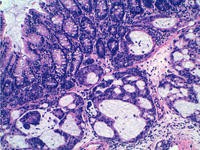

Un estudio coordinado por el investigador Manel Esteller, del Instituto de Investigación Biomédica de Bellvitge (IDIBELL) ha identificado una sustancia que inhibe el crecimiento del cáncer mediante la activación del llamado “genoma oscuro” (o ADN no-codificante) y de las moléculas de micro-ARN. El estudio se publica esta semana en la prestigiosa revista científica Proceedings of the National Academy of Science (PNAS).

Una parte de este ADN produce unas pequeñas moléculas denominadas microARN encargadas de activar o desactivar los genes. En los últimos años se ha demostrado que las alteraciones en estas moléculas están relacionadas con la formación de tumores. Los investigadores han demostrado que la pequeña molécula enoxacina, utilizada en compuestos antibacterianos, se une a la proteína que construye los micro-ARN y estimula su actividad inhibidora del crecimiento del tumor.